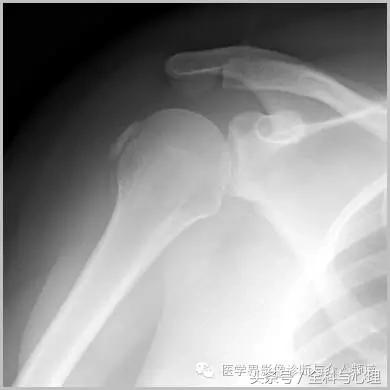

六、肌腱钙化/滑囊炎并钙化

肩关节最常见:肱二头肌长头、肩峰下滑囊钙化,可伴有急性疼痛、肿胀,局部压痛。

软组织钙化与骨化,软组织钙化和骨质增生 肱二头肌肌腱钙化(肩周炎)

软组织钙化与骨化,软组织钙化和骨质增生 肩周炎